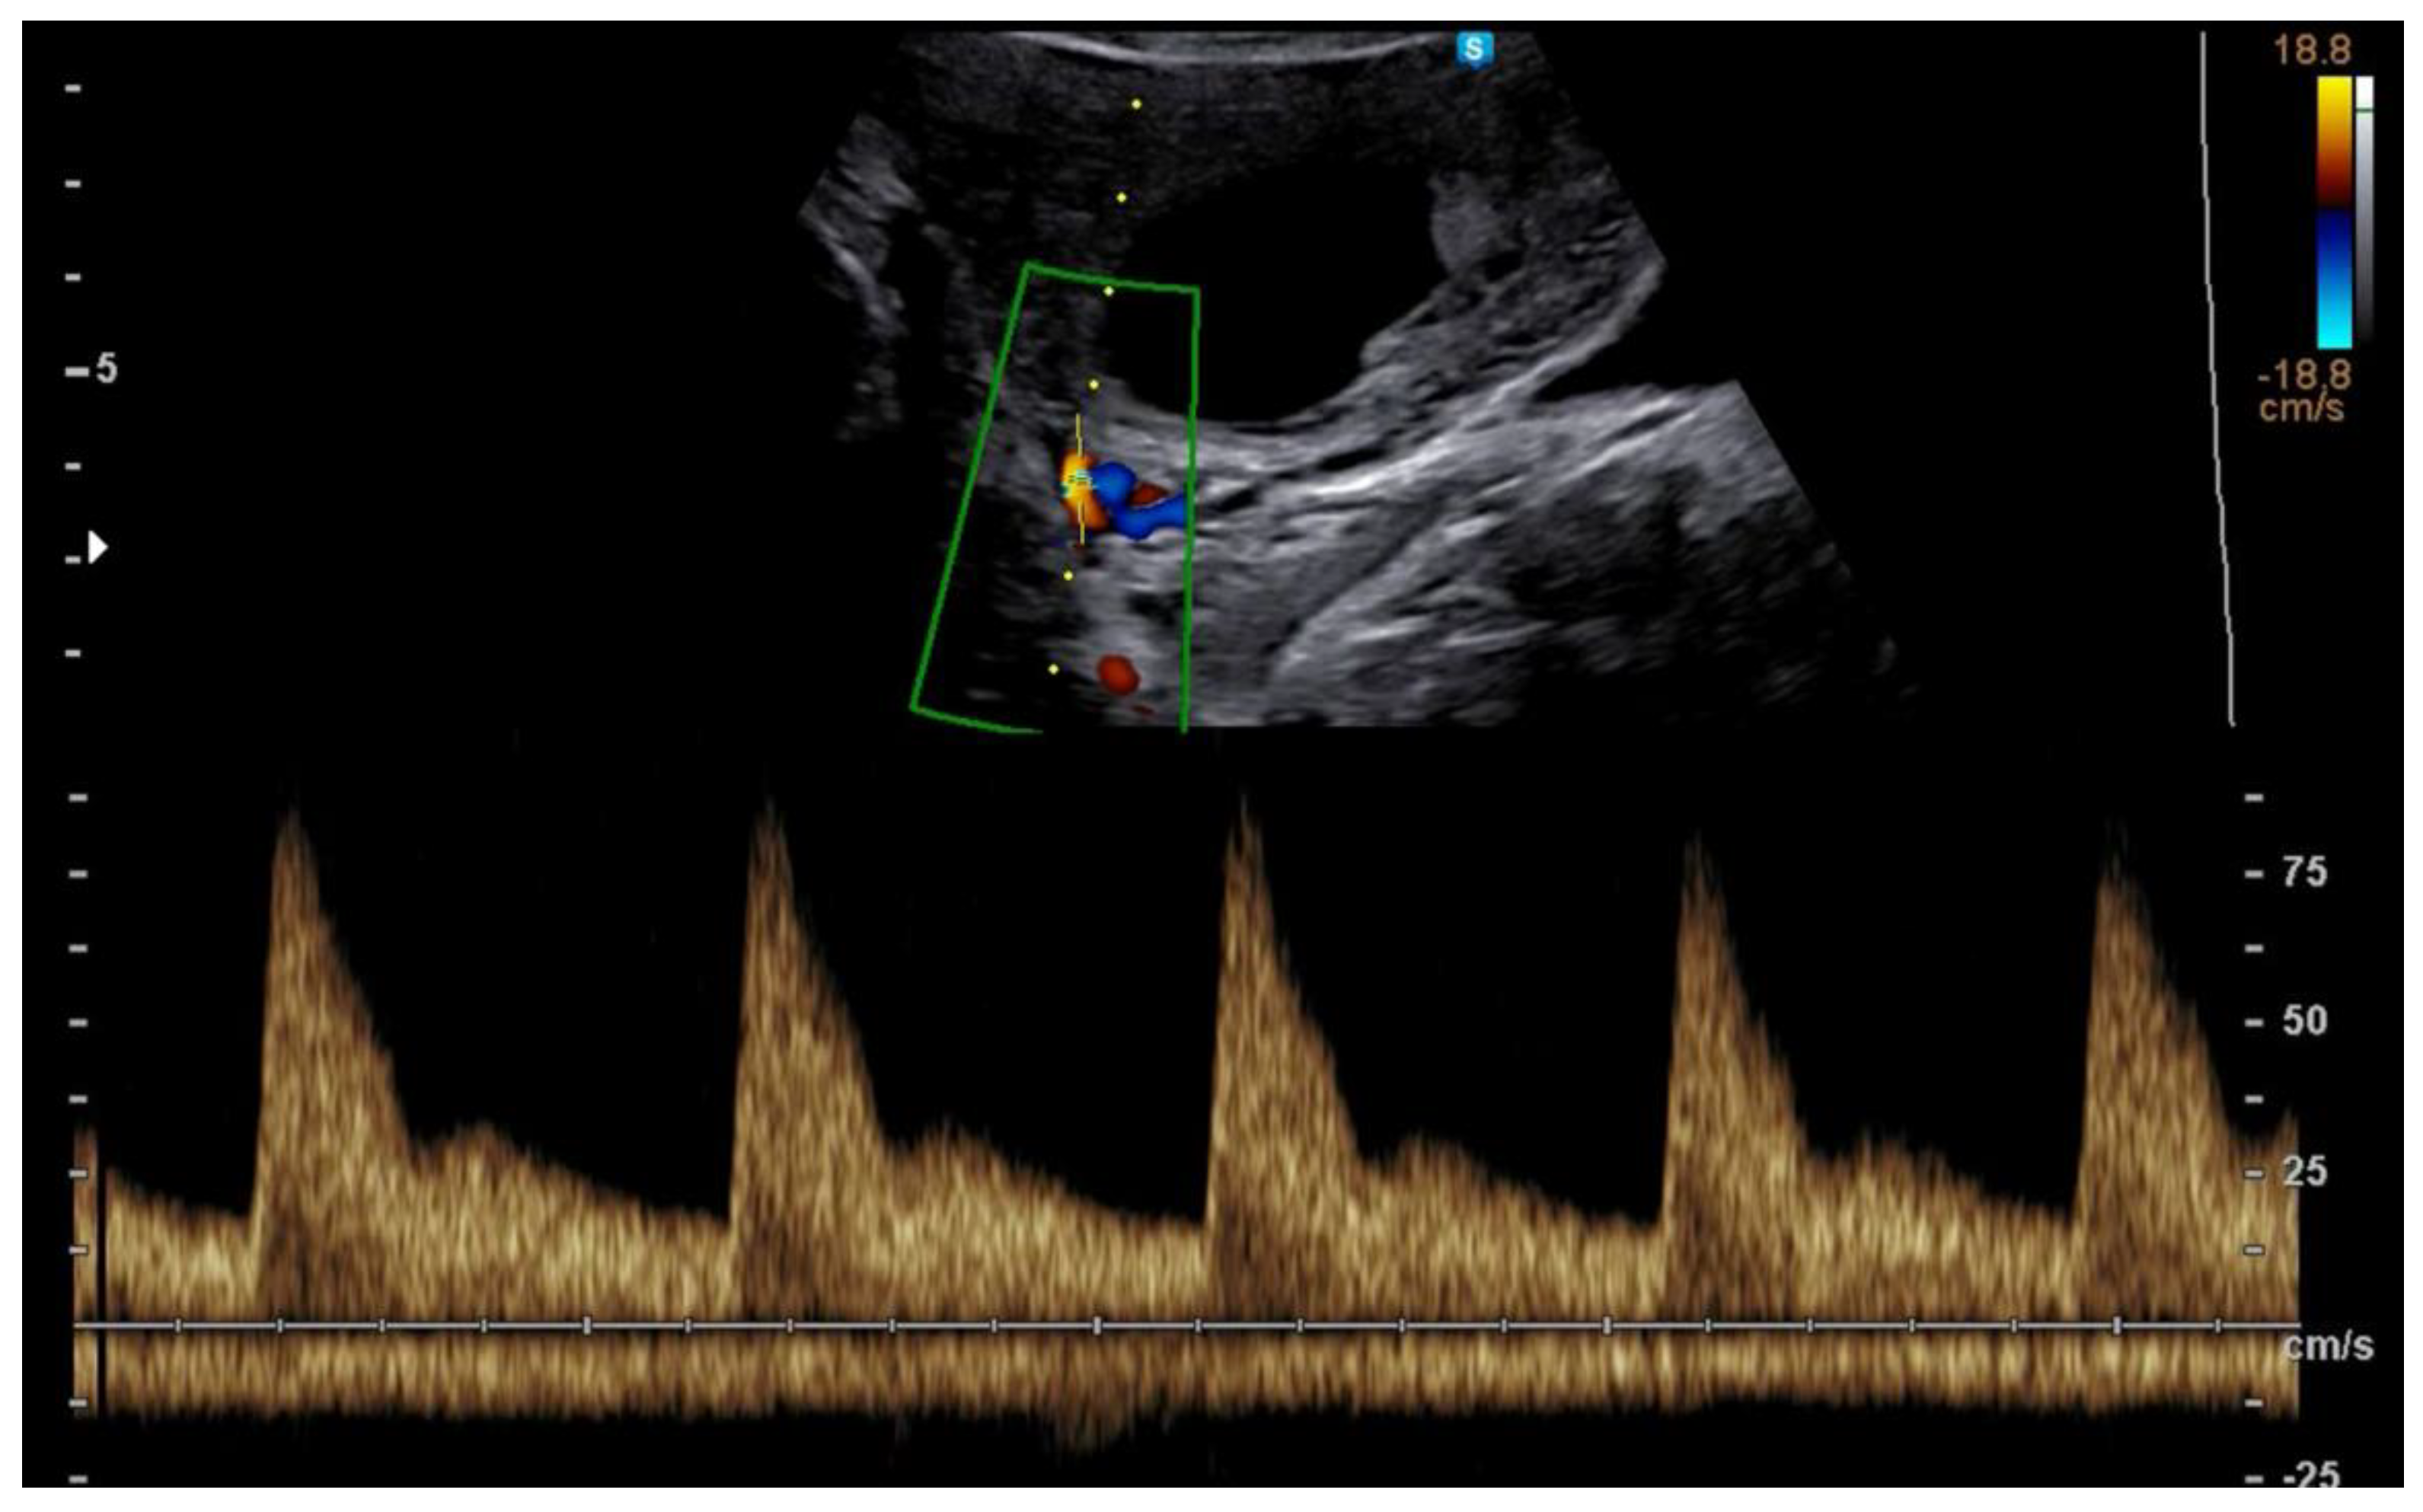

In a spontaneously conceived pregnancy, there is a decline of placental vascular resistance resulting in a progressive decrease of UtA-PI in the three trimesters of pregnancy (Figure 1) [45].

Figure 1.

Example of Doppler tracing obtained at 12 weeks from the uterine artery.

An impaired trophoblastic invasion of the uterine decidua indices an altered remodeling of the spiral arteries determines an increased vascular resistance in the uterine arteries already evident from 11 weeks onwards and it is frequently associated with a later development of PE [46,47,48]. Therefore, given the potential consequences of a higher incidence of placenta-related adverse outcomes in IVF pregnancies, the evaluation of impedance to flow in the uterine arteries in the context of in vitro fertilization was of particular interest.